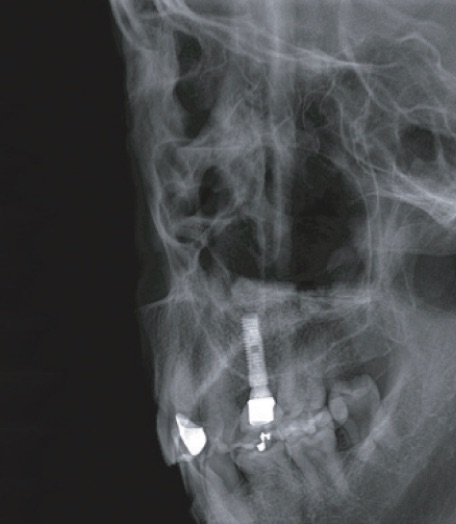

セファロ側方撮影

頭部一軸方向撮影